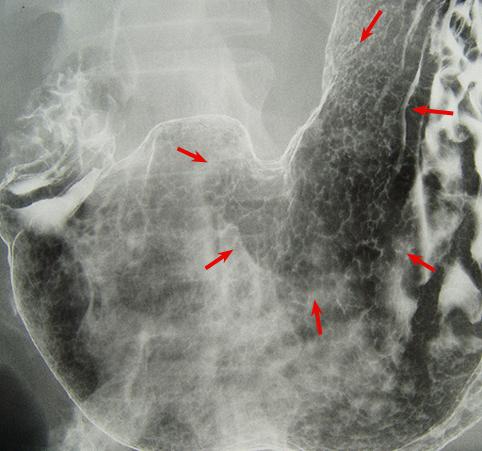

Criteria of Hist.ClassificationMalignant epithelial tumor/Adenocarcinoma

LocationStomach/Angle

Technique, MethodX-ray

Macroscopic TypesType 0/IIc (IIc) Superficial depressed type

Size30 - 34

Depth of Tumor Invasionmucosa